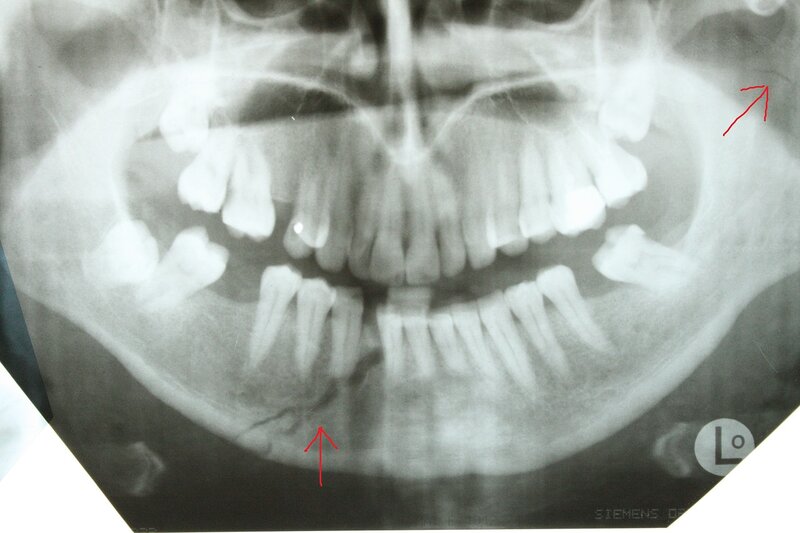

Зламана в результаті ДТП щелепа Адама Кадирова

Щелепа Адама Кадирова

Фото: NIYSO